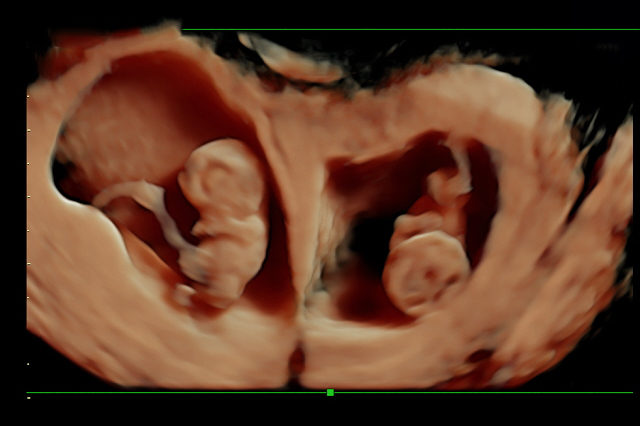

✔️ Twins / Triplets scan

✔️ Fetal growth scan 2D / 3D

✔️ Anomaly scan (4D scan)